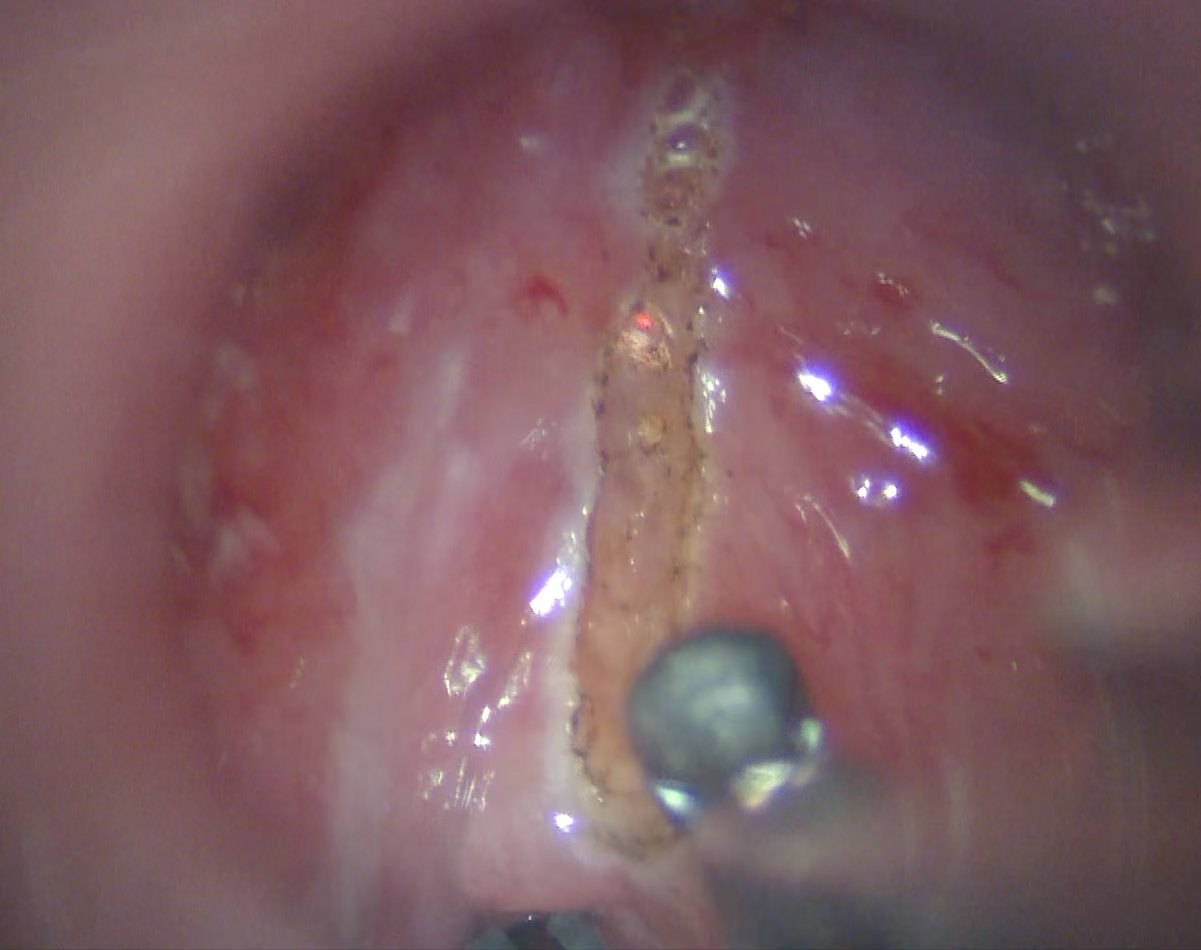

声带疾病(含咽喉早癌)的显微微创手术

由王刘倩医师团队牵头,该团队擅长使用显微镜辅助技术,对各类声带疾病进行精准的诊疗与手术。

其核心特色在于声带息肉切除术及激光切除血管性瘤或糜烂组织,这些方法能在最大限度保留声带本身结构和功能的情况下,彻底清除病变组织。

在显微缝合技术方面,该团队可精确到毫米级别,手术后患者能快速康复并持续改善发音质量。这种高超技艺使得王刘教授团队成为声带疾病治疗领域的佼佼者。